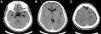

El paciente presenta una herida penetrante lumbar con salida de líquido cefalorraquídeo (LCR). La TC cerebral mostró la existencia de neumoencéfalo difuso (fig. 1). En los cortes axiales de la columna lumbar se observaba el trayecto del arma blanca a nivel de L1-L2 con enfisema subcutáneo asociado (fig. 2A).